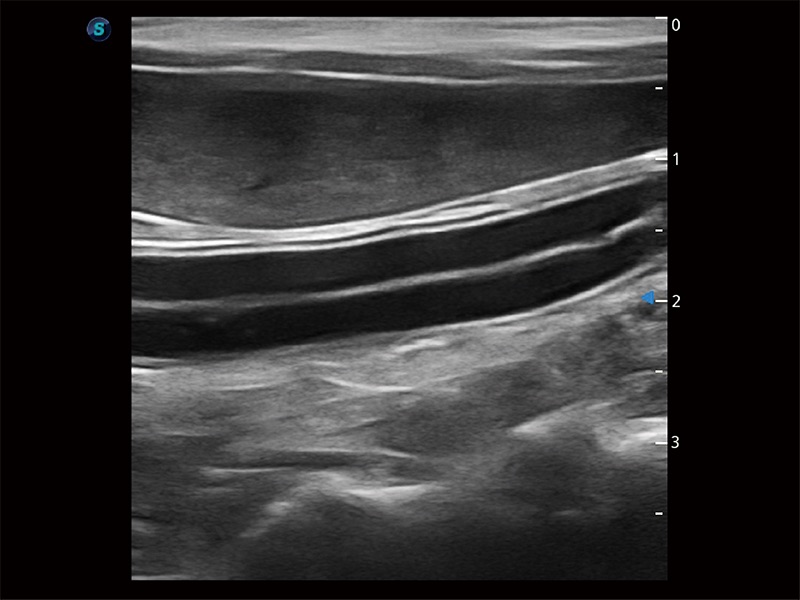

(犬)肝脏

(猫)胆囊

(猫)二尖瓣M型